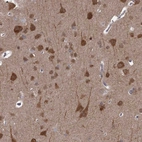

Immunohistochemical staining of human cerebral cortex shows strong cytoplasmic positivity in neuronal cells and moderate in neuropil.